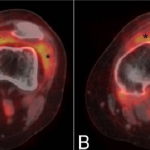

PET Imaging Reveals Subclinical Disease in Early Arthritis

Macrophage-targeting positron emission tomography (PET) may be a useful tool to detect subclinical synovitis in patients with early rheumatoid arthritis (RA), according to a new study. This PET technique could even distinguish between patients with and without a flare, the study suggested. A previous study found this approach promising for identifying subclinical synovitis … [Read more...] about PET Imaging Reveals Subclinical Disease in Early Arthritis